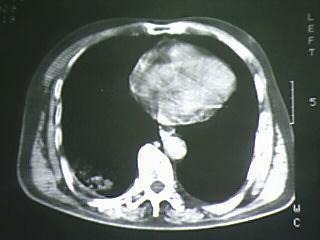

标题: CT19768:男 61岁 胸痛 咯血 一周。无发烧、无结核病史。 [打印本页]

标题: CT19768:男 61岁 胸痛 咯血 一周。无发烧、无结核病史。

右下肺中心型肺癌

右下肺支气管扩张

纵隔窗图像不佳,怀疑右下叶支气管有狭窄,来几张清楚的,暂考虑----感染性病变----抗炎后复查

考虑 右下肺感染性病变,建议抗炎后复查。

考虑右肺下叶感染性病变;建议抗炎治疗后复查。

考虑右肺下叶感染性病变,建议抗炎治疗后复查。

右下肺感染性病变,建议抗炎后复查。支持